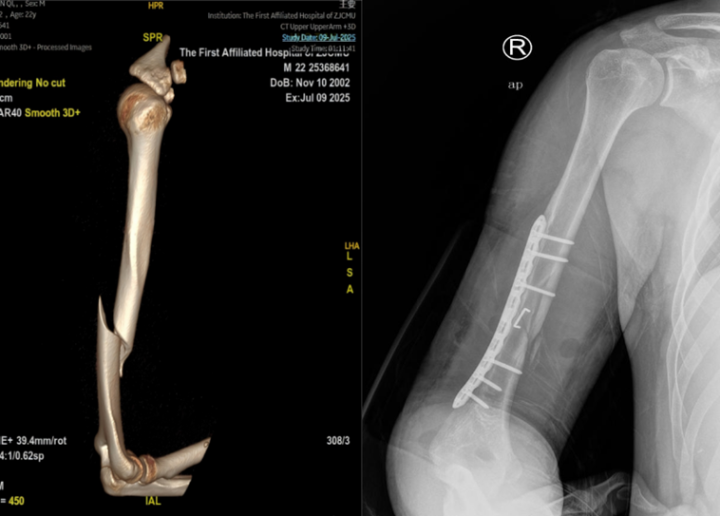

伴随着这声异响,一阵钻心的剧痛从阿琦右臂传来,他瞬间败下阵来,冷汗直流。此刻,输赢早已无人关心。朋友们被这突如其来的一幕吓坏了,赶紧将阿琦送往浙江省中医院钱塘院区。急诊骨伤科医生查体后发现阿琦的腕关节手指背伸困难,诊断结果让所有人倒吸一口凉气:“右肱骨干骨折,合并桡神经损伤!”

医生立刻为阿琦安排了手术,术中探查发现桡神经牵拉伤,延续性还在,没有断裂,整个手术过程也很顺利,但真正的考验才刚刚开始。在接下来的几个月里,阿琦的右臂需要佩戴支具长达一个月,并且要坚持至少半年的康复锻炼,以避免桡神经损伤留下后遗症。手臂功能的受限,也给他的学习和生活带来了极大的不便。